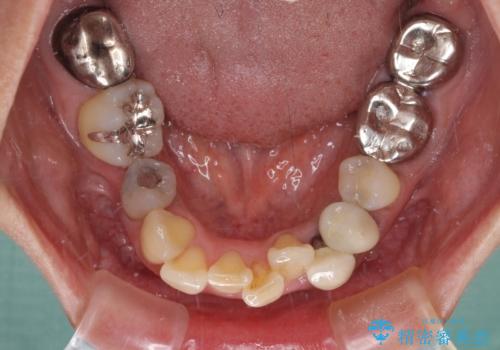

- 非対称な前歯や奥歯の目立つ銀歯を気にして来院された患者様です。

左上前から2番目の歯は、以前裏側に位置していたことから抜歯をされていましたが、前歯の非対称が長年気になっているとのことでした。

矯正治療によって前歯にスペースを作り、左右対称となるようにオールセラミッククラウンにて補綴治療を行うとしました。

他にも奥歯の咬み合わせに問題があったので、全顎的な矯正治療を行い、前歯以外にも口を開けたときに目立つ奥の銀歯をセラミッククラウンにて補綴治療を行うこととしました。